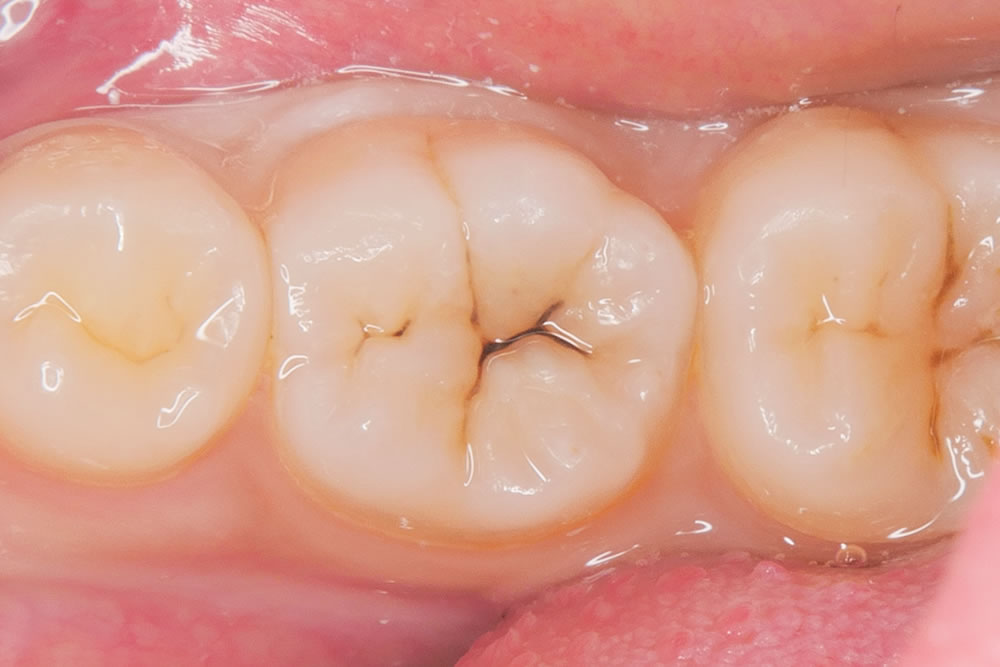

治療完了

形態修正と研磨を行い、治療が終わりました。

治療前後の比較